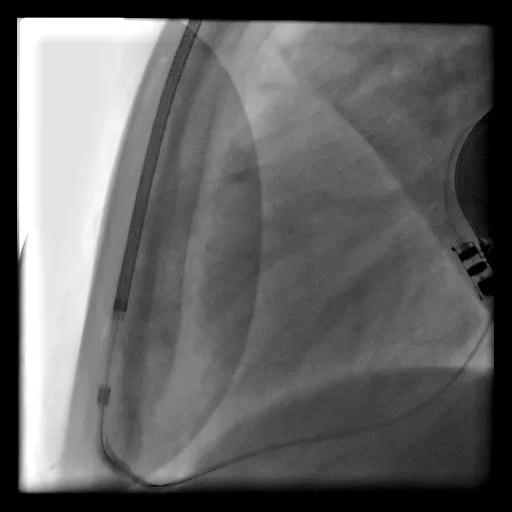

2021年1月6日,上海交通大学医学院附属瑞金医院心脏内科成功为一位20岁女性扩张性心肌病患者植入该院首例全皮下植入式心律转复除颤器(S-ICD)。